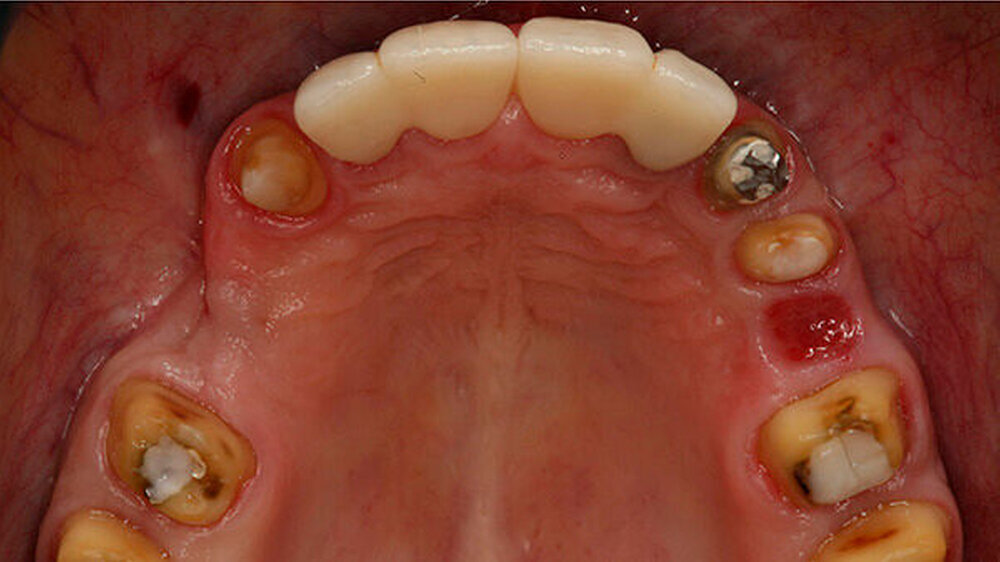

Beispiele für individuellen ZE

Die Jahrestagung der Deutschen Gesellschaft für Prothetische Zahnmedizin und Biomaterialien (PGPro) in Ulm geht der Frage nach, welche Versorgungskonzepte - mit guten Langzeitergebnissen - individuell und preiswert machbar sind. Gute Beispiele finden Sie in unserer Bilderstrecke!